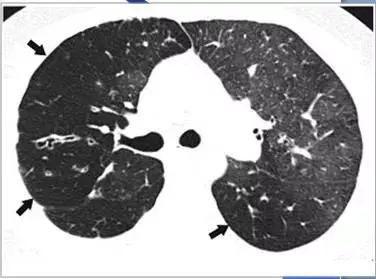

CT征象八:碎石路征

碎石路征(Crazy paving appearance):在HRCT上,表现为地图状分布的、重叠有网状的光滑细线影的磨玻璃影;最常见于肺泡蛋白沉着征。

细线影为小叶间隔水肿增厚,或蛋白样物质沉积于邻近小叶间隔的气腔内所致。

碎石路征(Crazy paving appearance)

碎石路征:肺泡蛋白沉着症(PAP)